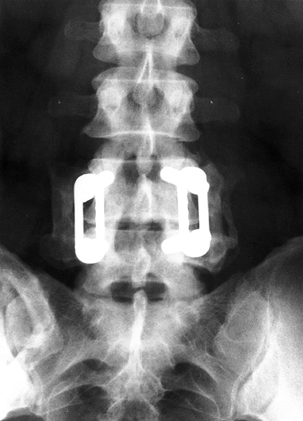

posterolateral fusion procedures in an attempt to decrease

pseudarthrosis rates (Fig. 145.13, Fig. 145.14).

Data from fusion procedures for degenerative spondylolisthesis suggest

increased fusion rates but no effect on clinical outcome (19).

Instrumentation is associated with higher costs and complication rates.

One recent series noted 10% of patients had instrumentation-related

problems. Yet, biomechanical studies suggest that pedicle screw

constructs are superior in stabilizing the nonosteoporotic spine (31).

These constructs may confer immediate stability to motion segments and

allow an expedited postoperative recovery. This added stiffness and

faster recovery interval may be more important in the younger

population with DDD than in the older patient with degenerative

spondylolisthesis.

![]() |

|

Figure 145.14. Postoperative lateral radiograph depicting fusion with instrumentation at L3-4.

Figure 145.13. Postoperative AP radiograph after single-level L4-5 posterior fusion with instrumentation.